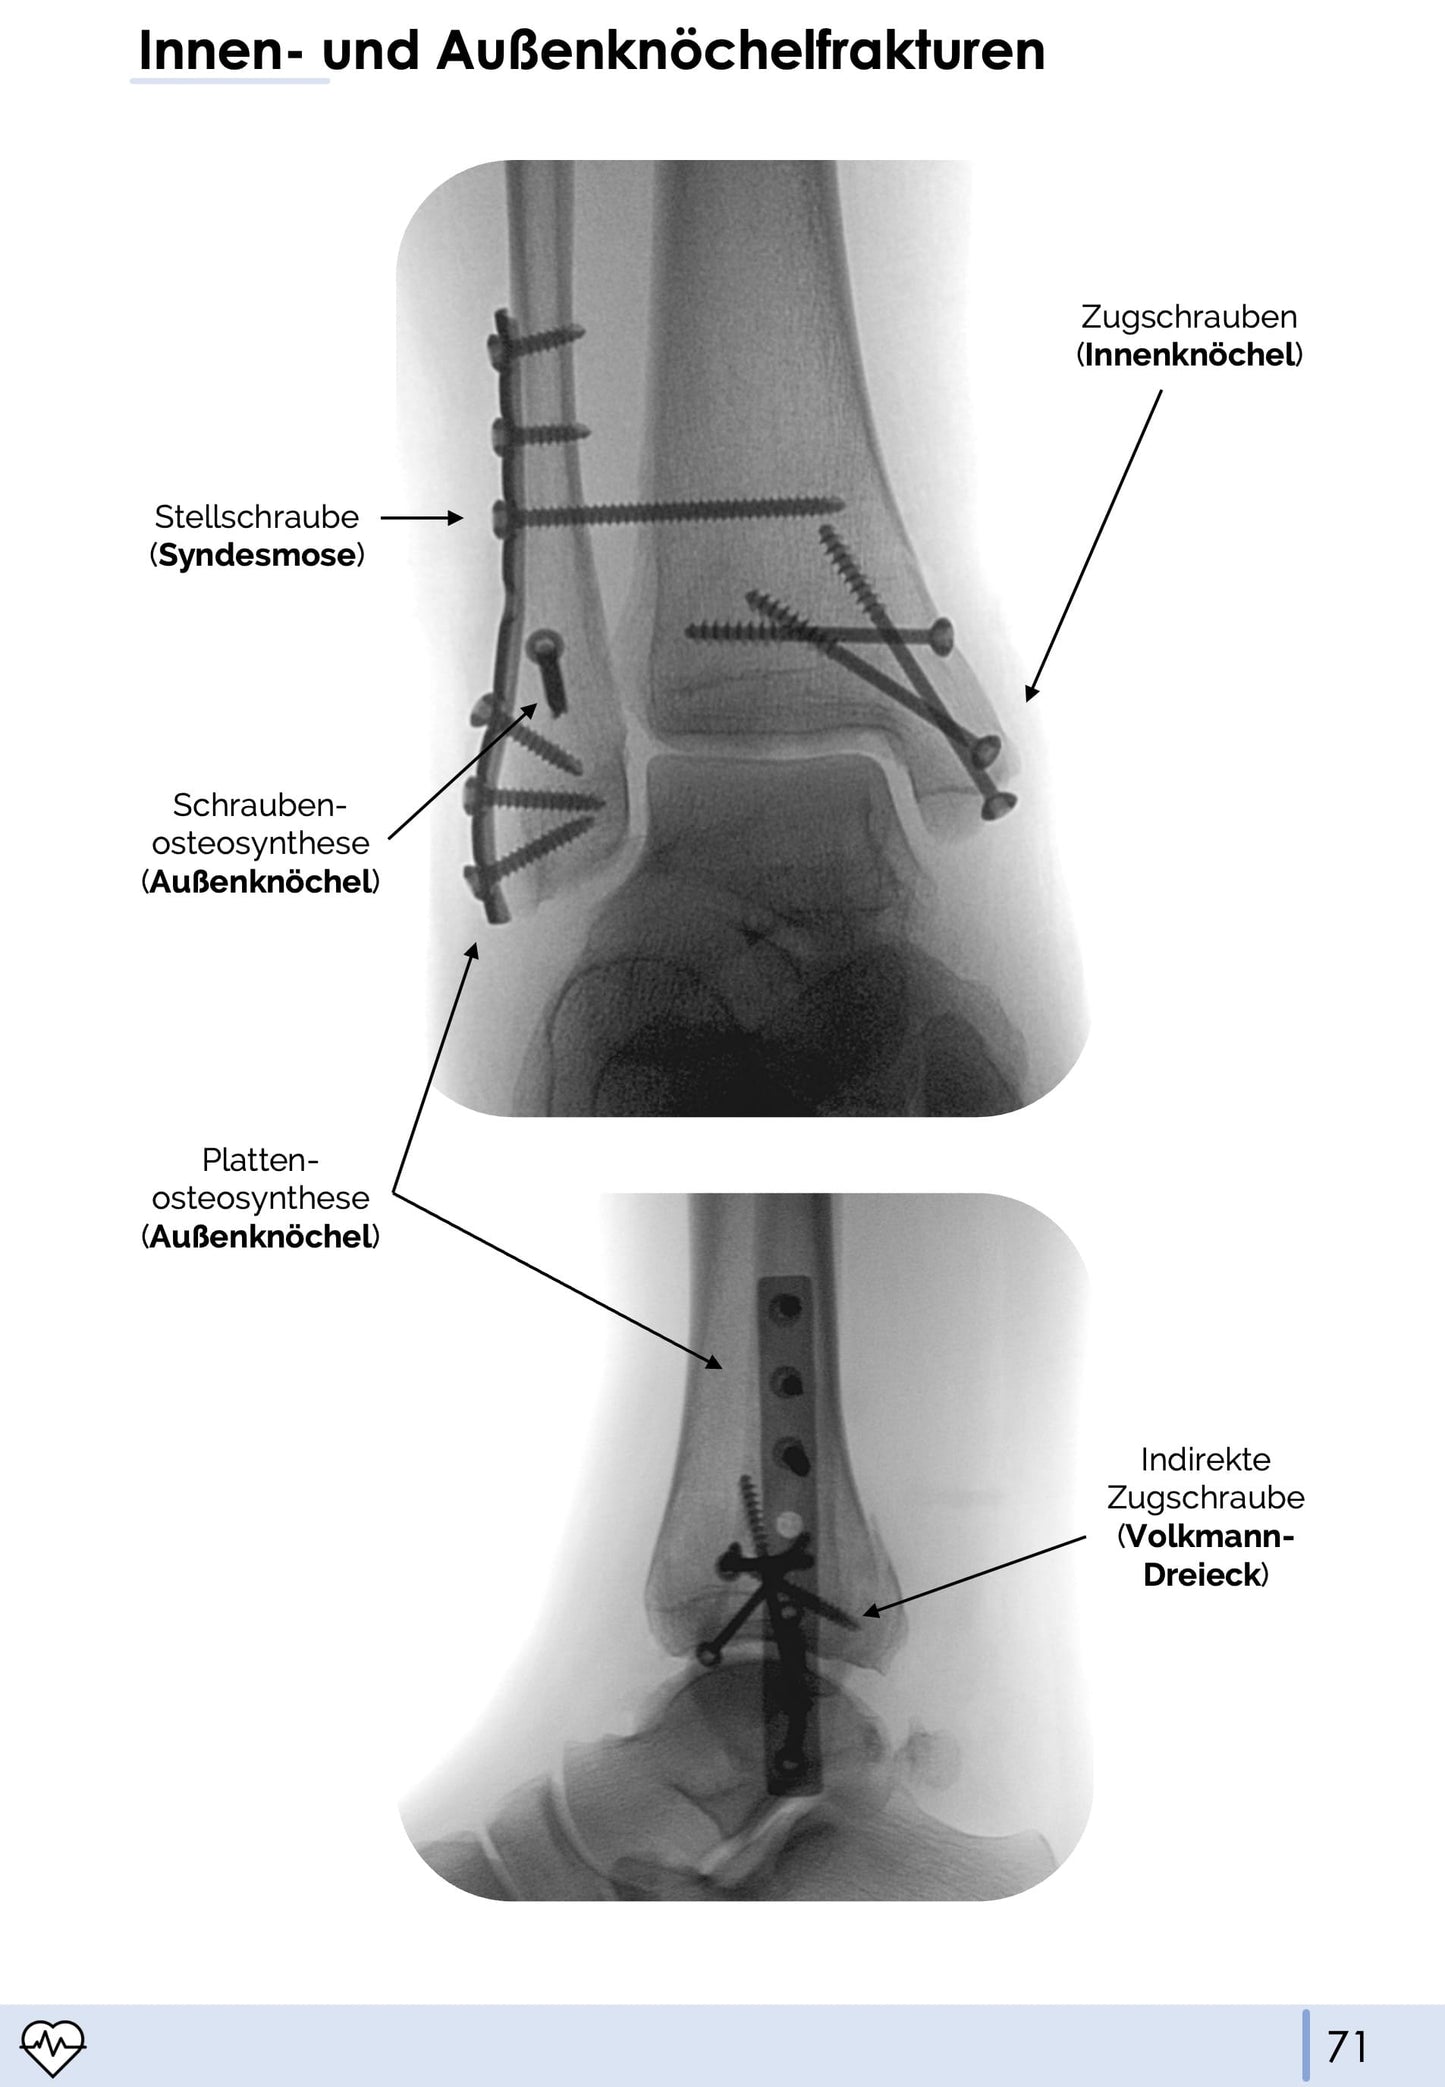

Stell dir vor, dein erster Tag in der Unfallchirurgie steht bevor! Vielleicht hast du schon grob gelernt, welche Frakturen es gibt und was eine Plattenosteosynthese ist, so richtig Ahnung was zu tun ist, hast du jedoch nicht. In unserem Unfallchirurgie und Orthopädie-Skript gehen wir auf die wichtigen Frakturen und deren Behandlung ein. Wir haben bei dem Skript den Fokus auf Praxisorientiertheit gelegt. Daher haben wir zu den wichtigen Frakturen und Behandlungsarten beschriftete und markierte Röntgenbilder hinzugefügt, sodass euch das Skript nicht nur für die theoretische Prüfung, sondern auch im Berufsalltag etwas bringt.

- 💪🏼 Praxisorientiert mit vielen beschrifteten Röntgenbildern und praktischen Tipps

- Innen- und Außenknöchelfrakturen (AO 44)

- Viele echte Röntgenbilder mit Markierungen

- Klassifikationen und Therapieoptionen visualisiert dargestellt